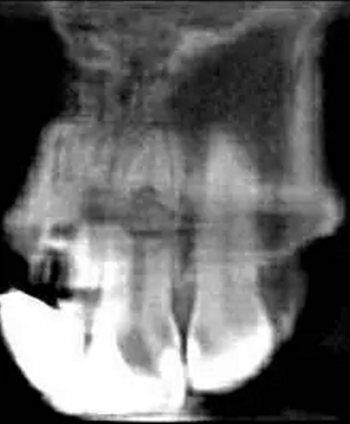

左上中切牙近遠(yuǎn)中有牙色充填體,邊緣繼發(fā)齲,牙齒不松動(dòng),輕微叩痛,患牙冷測(cè)遲鈍,牙齦未見異常。X線片示:充填體周圍繼發(fā)齲壞近髓,根中部大面積低密度影,蟲噬狀,內(nèi)部結(jié)構(gòu)顯示不清晰,根尖周未見異常。錐形束CT(CBCT)顯示根中部?jī)?nèi)吸收多處可疑穿孔,缺損內(nèi)可見菜花狀鈣化物影像

診斷:左上中切牙牙根內(nèi)吸收。治療計(jì)劃:左上中切牙根管治療,全冠修復(fù)。 治療過程:患者知情同意。使用含1/100,000腎上腺素的4%鹽酸阿替卡因(碧蘭麻,艾龍)局部浸潤(rùn)麻醉,橡皮障隔濕。去腐未盡露髓,露髓孔出血多。開髓,使用10#不銹鋼K銼(MANI,日本)探查根管,根管中段有鈣化物阻擋,不能達(dá)到牙根全長(zhǎng)(圖3A)。在顯微鏡下(Leica M400E,萊卡, 德國(guó)) 使用超聲尖(E1根管治療超聲尖,啄木鳥公司,中國(guó))通開,采用根管長(zhǎng)度測(cè)量?jī)x(Root ZX, Morita公司,日本)加診斷絲片法(圖1B)測(cè)量根管長(zhǎng)22 mm。使用控制扭矩馬達(dá)(X-smart,登士柏)和鎳鈦旋轉(zhuǎn)器械(Hero 642, Micromega)根管預(yù)備,根管預(yù)備過程中使用5.25%次氯酸鈉溶液沖洗。 根備完成后使用超聲蕩洗根管,5.25%次氯酸鈉溶液3 分鐘, 17% EDTA溶液1分鐘。干燥根管,使用螺旋充填器根管內(nèi)封氫氧化鈣糊,氧化鋅丁香油水門汀暫封。1周后患者復(fù)診,患者述無術(shù)后不適,檢查暫封完好,無叩痛,不松,牙齦無紅腫瘺管。使用橡皮障隔濕,去除暫封物,超聲蕩洗根管,5.25%次氯酸鈉溶液3 分鐘, 17% EDTA溶液1分鐘。干燥根管,牙膠尖(達(dá)雅鼎,中國(guó))和必蘭根充糊劑(Cortisomol, 艾龍公司,法國(guó))熱垂直加壓法根管充填。術(shù)后片顯示根充恰填,可見牙膠/糊劑被壓入鈣化物周圍和內(nèi)部縫隙內(nèi)

1月后復(fù)查無不適,行全瓷冠修復(fù)。8月2周后復(fù)查,患者無不適主訴,牙冠美觀,邊緣完好,患牙無叩痛,不松動(dòng),牙齦無紅腫瘺管, X線片示根周膜連續(xù),根尖周未見異常。建議患者避免用前牙撕咬食物,定期復(fù)查。 討論: 臨床上,由于牙根內(nèi)吸收和牙根外吸收的治療方法和預(yù)后不同,常需要對(duì)兩者進(jìn)行鑒別診斷。過去通常采用偏移投照的方法鑒別兩者。在偏移投照片上,外吸收病損和根管輪廓相對(duì)位置較正位片會(huì)發(fā)生變化,而內(nèi)吸收病損則不會(huì)[12]。